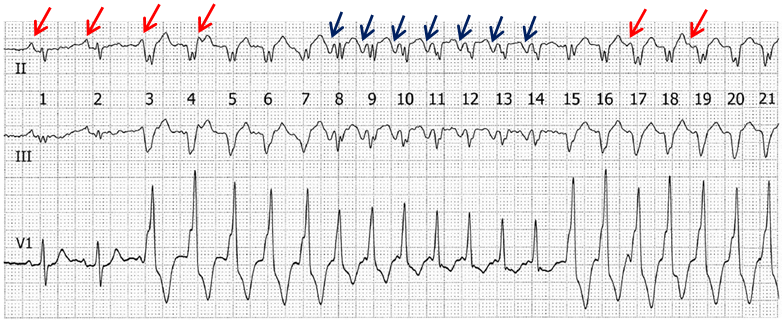

该心电图记录自一名58岁中年男性运动试验的恢复阶段(图1)。今天的重点在于"赏图",其他资料不做过多介绍。一眼望去,整个心电图有宽有窄,错落有致。1~2跳为窄QRS波,是窦性心律;3~7跳为宽QRS波;8~14跳为窄QRS波;15~21跳为宽QRS波,形成类似"夹心饼干"样的变化。图中基础PP间期约为620 ms,3~7跳宽QRS波心动过速RR间期约为300-340 ms,8~14跳窄QRS波心动过速的RR间期约为260-300 ms,15~21跳宽QRS波心动过速的RR间期约为280-300 ms。熟悉但棘手的问题来了,上述心动过速的机制是什么?

图1 心电图提示宽窄QRS波交替,形成类似"夹心饼干"样结构,红色箭头和蓝色箭头标记了两种不同形态的P波

既然心电图已天然形成了宽窄QRS波交替的规律,我们就逐一看过去。前2跳为窄QRS波,其前可见明确P波,PR间期约为150 ms,考虑为窦性激动。而第3跳,为宽QRS波,其前可见P波的一部分,其余部分重叠在QRS波内,P波和QRS波无传导关系,因而第3跳起源自心室。第4~7跳和15~21跳均为宽QRS波心动过速,形态类似,其中第4跳终末、17跳起始和19跳起始前,可见P波(红色箭头指示),测量PP间期固定,在620 ms左右,也就是说在宽QRS波心动过速发生时,窦性心律并未受到影响,专业术语叫做"房室分离"。房室分离的存在,提示宽QRS波心动过速为室速。那么,中间的窄QRS波心动过速又是什么?

对于窄QRS波心动过速,每个QRS波之前,都有一个倒置的P波(蓝色箭头所示)。P波和其前及其后的R波关系都是固定的,RP约为260 ms,PR约为100 ms。第7跳"逆传P波"后心动过速发作,第14跳"逆传P波"消失后心动过速终止。这些特点提示,窄QRS波心动过速为阵发性室上性心动过速。因其RP > PR,因而为长RP的阵发性室上速。

注意8~14跳的QRS波形态,并不完全一致,有的略窄,有的略宽,如果只是单纯的房室结折返性心动过速,不应该存在这种变化。一种合理的解释就是,这几跳中,存在融合波,也就是这些QRS波都是房室结折返性心动过速下传心室和室速"融合"的结果。房室结折返性心动过速发作时,室速也在发作,房室结折返性心动过速下传心室较快,在"合资"中占主导地位,因而总体QRS波较窄,房室结折返性心动过速下传心室越快,占有比例越大,QRS波越窄。为了便于理解,可参照图2的梯形图。